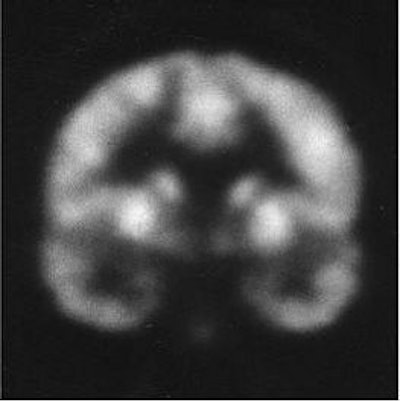

![]() |

| Coronal MR scans from a chronic schizophrenic (above) and normal comparison subject (below). Note increase in CSF in left amygdala-hippocampal complex. Images courtesy of Schizophrenia Research Project and Psychiatry Neuroimaging Laboratory, Harvard University, Boston. |